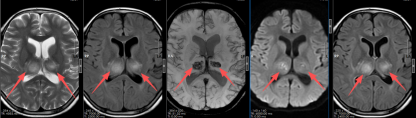

“入院时,立即转入了重症医学科。”该院神经内一科副主任匡祖颖接诊后,完善MR检查后发现患儿脑干、双侧丘脑、双侧基底节、右侧小脑、双侧顶叶区部分脑沟多发病灶,正规杠杆炒股平台最终诊断患儿是急性坏死性脑病。

入院时影像显示多发病灶